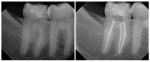

The simple and logical progression of the Basic and Advanced ESX instrumentation protocols is a product of the superior manufacturing quality of the established EndoSequence File, along with the addition of two new features: advanced BT-Tip Technology and a new, logical, and safe Single Stroke and Clean operator motion that makes the new ESX File System both efficient and simple for clinicians performing root canal therapy with basic or advanced protocol (Figure 5 and Figure 6).